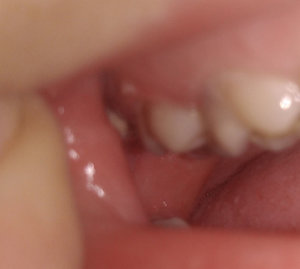

4 месяца назад мне сделали вкладку на предпоследний зуб нижней челюсти, при этом рядом стоящий ближний зуб удалили, т.к. было нагноение на десне. Я не сделала коронку на один зуб, т.к. хотела закрыть просвет и от недостающего зуба. Но и стачивать ближний зуб (здоровый) мне не хотелось. На дорогой имплант средств не нашлось. Сейчас зуб со вкладкой стал побаливать и на десне снова появилось нагноение. Из-за чего это произошло и что мне теперь делать? Явилось ли моё промедление результатом нагноения или это могло произойти и под коронкой?